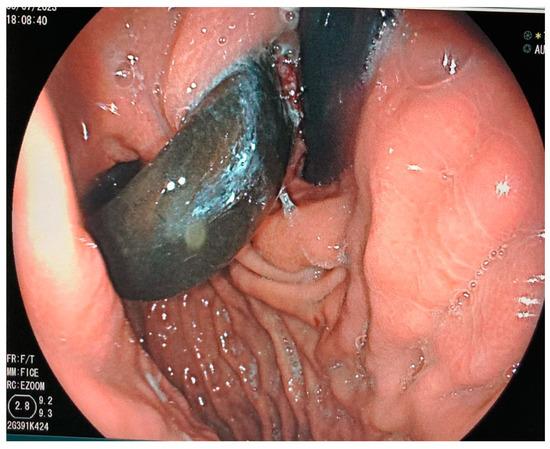

- Dugan, J.; Bajwa, K.; Singhal, S. Endoscopic removal of gastric band by use of a stent-induced erosion technique. Gastrointest. Endosc. 2016, 83, 654–655. [Google Scholar] [CrossRef]

- Manos, T.; Nedelcu, A.; Noel, P.; Zulian, V.; Danan, M.; Vilallonga, R.; Carandina, S.; Nedelcu, M. Endoscopic Gastric Band Removal. J. Clin. Med. 2023, 12, 617. [Google Scholar] [CrossRef] [PubMed]

- Dellaportas, D.; Nastos, C.; Theodosopoulos, T.; Fragulidis, G.; Polydorou, A.; Vezakis, A. Novel Endoscopic Management of Eroding Laparoscopic Adjustable Gastric Band: A Case Series. Case. Rep. Gastrointest. Med. 2018, 2018, 2747852. [Google Scholar] [CrossRef] [PubMed]

- Neto, M.P.; Ramos, A.C.; Campos, J.M.; Murakami, A.H.; Falcao, M.; Moura, E.H.; Evangelista, L.F.; Escalona, A.; Zundel, N. Endoscopic removal of eroded adjustable gastric band: Lessons learned after 5 years and 78 cases. Surg. Obes. Relat. Dis. 2010, 6, 423–427. [Google Scholar] [CrossRef] [PubMed]

- Chisholm, J.; Kitan, N.; Toouli, J.; Kow, L. Gastric band erosion in 63 cases: Endoscopic removal and rebanding evaluated. Obes. Surg. 2011, 21, 1676–1681. [Google Scholar] [CrossRef] [PubMed]